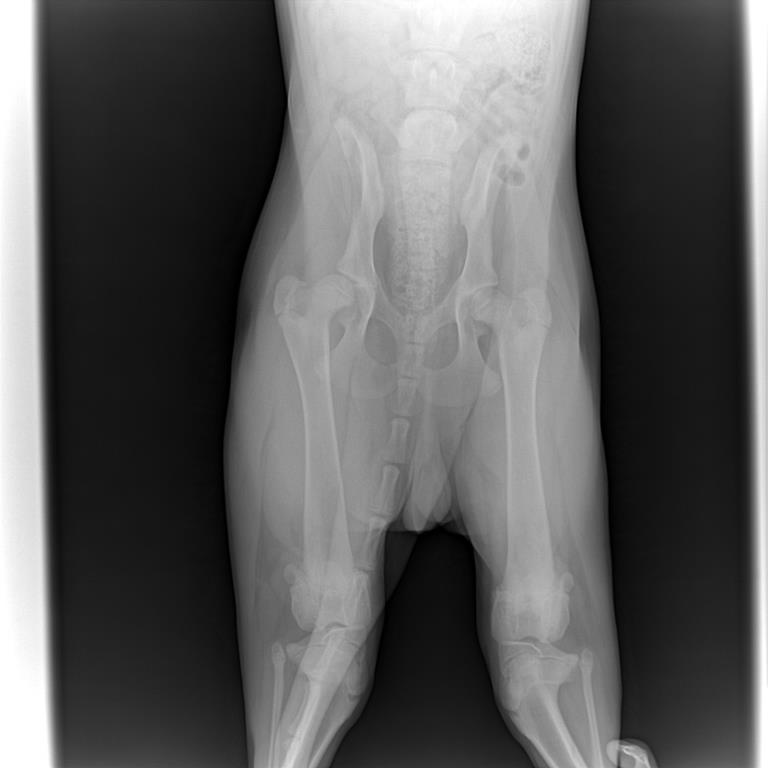

Здравствуйте! Подскажите пожалуйста,что делать. Взяли щенка немецкой овчарки в возрасте одного месяца. Все было хорошо. Когда хотели отдать на дрессировку нам сказали проверить ножки на дисплазию. Снимок делали в 4,5 месяца.Врач поставил дисплазию. В таком возрасте можно ставить точный диагноз? К сожалению снимки не подписали.

Вложения

124722_0harvi.jpg

124725_01harvi.jpg

То,что видно по снимкам-дисплазия имеется. Но лечение и указания должен назначать врач,учитывая состояние собаки и наличие или отсутствие других симптомов.

Насчет возраста-обычно с возрастом становится хуже,а не наоборот.